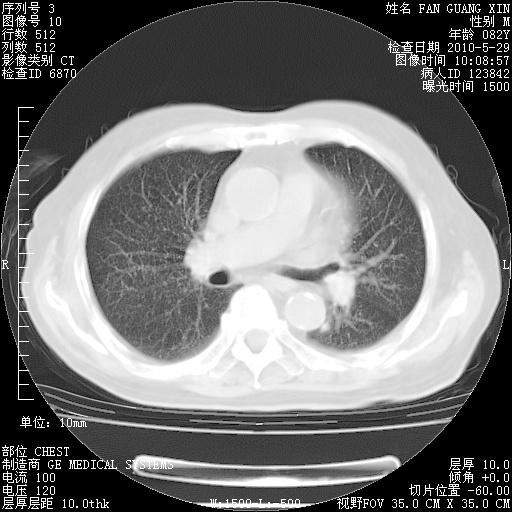

治疗3周后的肺部CT纵隔窗

再治疗10天后的肺部CT